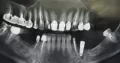

Справа наблюдается перфорация корня. Зуб, к сожалению, удаляется по всем показаниям. 4 необходимо перелечить и установить мостик с 6 по 4 зуб, либо установить одиночную коронку на 4, а на место удаленной 5 установить имплантат.

Слева все намного хуже: 5 удаляется, так как имеет грануляцию на верхушке корня, в области 6 зуба наблюдаем материал за верхушкой корня, к тому же в области пазухи. Необходимо проделать операцию по извлечению материала, сам зуб под вопросом.

Уважаемый пациент, у вас очень много проблем на нижней челюсти и в ближайшее время вас ждут обязательные процедуры. Справа — удаление 8, 6, 5 зуба, 4 можно спасти, слева 5, 7, 8 необходимо перелечить и чем раньше вы этим займетесь, тем больше вероятность сохранение зубов.